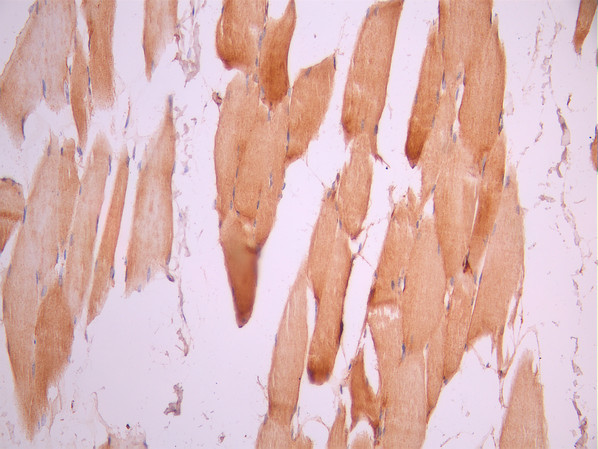

• IHC image of CSB-RA062281A0HU diluted at 1:100 and staining in paraffin-embedded human skeletal muscle tissue performed on a Leica BondTM system. After dewaxing and hydration, antigen retrieval was mediated by high pressure in a citrate buffer (pH 6.0). Section was blocked with 10% normal goat serum 30min at RT. Then primary antibody (1% BSA) was incubated at 4°C overnight. The primary is detected by a Goat anti-rabbit polymer IgG labeled by HRP and visualized using 0.05% DAB.